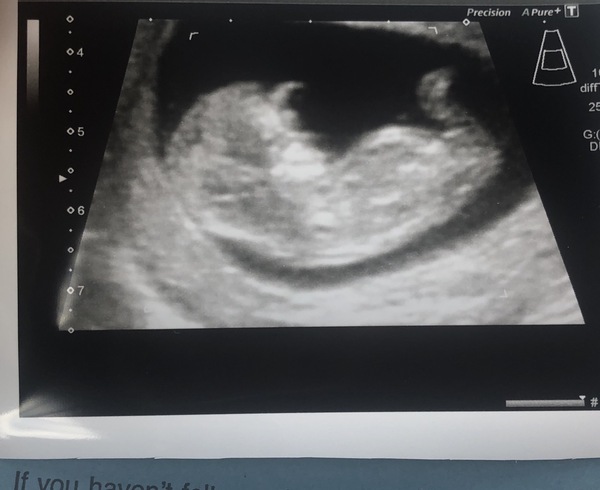

Oops so I realised my scan photo had all my details on it 🤦🏽‍♀️

So just reposting -

Happy news here! Baby measuring 13 weeks but been given a due date of 2 May - how does that work?! Anyway also had the harmony test results back, I’m 1/10,000 for all three trisomy conditions so super low risk! I am so happy! And just found out I’m having a little girl 💖 absolutely thrilled!! So much lovely news in one day x

@sunshine8888 lovely scan pic! You would think your due date would be 28th April based on scan, did they mention why they dated 2nd May? Either way if its April its a few days closer to meeting little one

Thank you, good luck to those having scans today and look forward to seeing some more scan pics ☺️ For those trying to guess gender on nub and skill pic, my pic is above and it’s a little girl if that helps at all ☺️